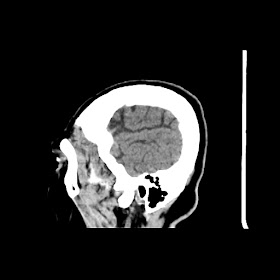

A 75 years old woman with DM-2 since 3 years

Patient O/E images:

C/O: Breathlessness X 2-3 day's

H/O: unconsiouness since few hour's at home around 10:30 pm

K/C: DM / HTN since 2-3 year's